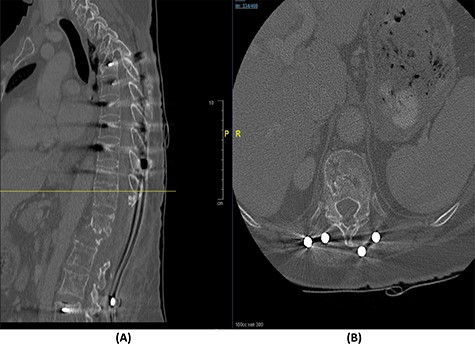

Radiological and laboratory investigations for possible malignancy or infection were done, and results were negative for malignancy. Erythrocyte sedimentation rate (ESR) was 50 mm/h and C-reactive protein (CRP) level was 38 mg/l. A magnetic resonance imaging (MRI) scan of the spine with contrast showed a significant pathological fracture of L1 along with spinal cord compression (Fig. 1). The patient underwent posterior spinal decompression of T12–L1 and pedicle instrumentation of T11–L3 with tissue and bone biopsy.

(A) T2-weighted sagittal lumbar spine MRI demonstrating a pathological fracture of L1 with spinal canal and neural foramina stenosis and cord edema and epidural and prevertebral soft tissue components. (B) T2-weighted axial lumbar spine MRI of the corresponding level of L1 vertebral body.